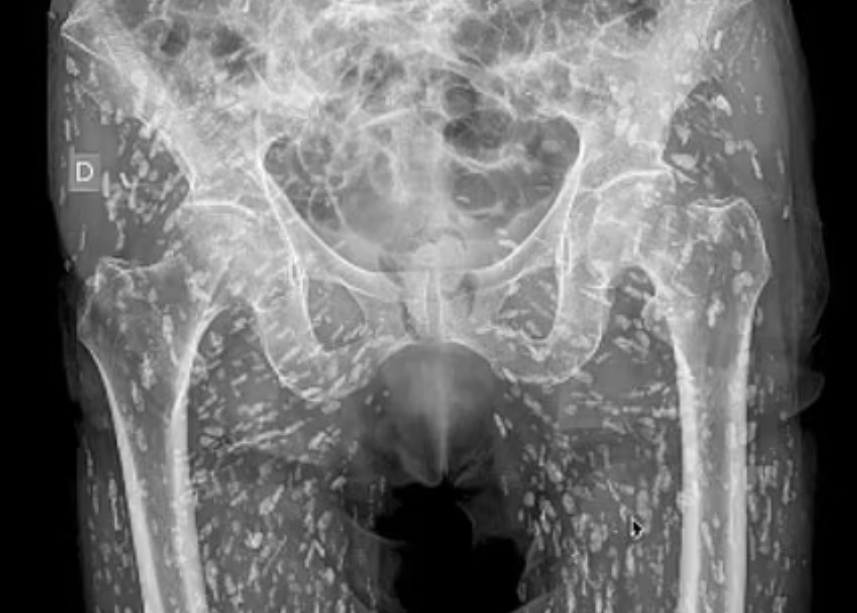

The image shows hundreds of 'rice grain' nodules that turned out to be cysts caused by the parasitic infection.

Dr Sam Ghali, an urgent care doctor in Florida, shared the photo on social media describing it as one of the 'most insane X-rays' he'd ever seen.

In a video that has went viral, a shocked Dr Ghali says: 'They're everywhere [the cysts] and they're innumerable, you can't even begin to count them all.

'Now these cysts can travel anywhere throughout the entire body. In this patient, they've traveled heavily to the soft tissues of the hips and the legs.'